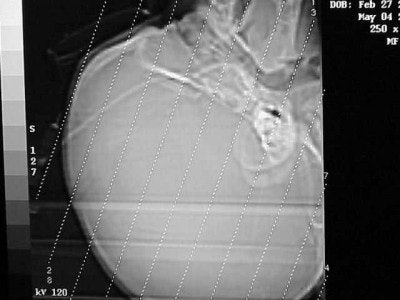

As for blunt-force trauma, say you have a child who is a suspected victim of child abuse (non-accidental trauma). Doctors are looking for an inter-cerebral bleed but nothing is obvious on the axial scan. Are there alternatives?

If the c-spine is cleared, then extend the child’s head as in a reverse coronal position (Figure CT 3). If the c-spine is not cleared, then you can affix the child to a backboard and tilt the foot of the board up about 30°-45° or so. Scans through the brain, if positive, will show blood collecting in the superior convexity (Figure CT 4), an almost definite sign of non-accidental trauma.

![]() |

| Figure CT 3 |

| Figure CT 4 |